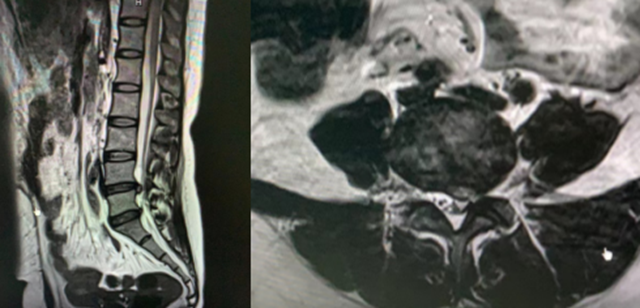

原来,刘嬢嬢10多年来被腰痛折磨得苦不堪言,最近10天明显加重,因为腰痛牵扯到左下肢,导致行走困难,到多家医院就诊,确诊为腰椎间盘突出症,经各种保守治疗,效果均不理想,遭老罪了。

经过门诊详细检查,发现刘嬢嬢纤维环破裂,神经根受压明显。经科室刘庆教授、张英教授等会诊后,决定予以“椎间孔镜手术”。

椎间孔镜与脊柱内窥镜类似,是一个配备有灯光的管子,它从病人身体侧方或者侧后方进入椎间孔,在安全工作三角区实施手术。在椎间盘纤维环之外做手术,在内窥镜直视下可以清楚地看到突出的髓核、神经根、硬膜囊和增生的骨组织,然后使用各类抓钳摘除突出组织、镜下去除骨质、射频电极修复破损纤维环。